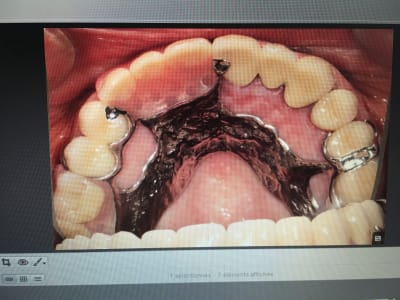

IC ceram 23 + stellite.

Plus longtemps que les dents restantes de l'autre coté. La patiente ne voulait pas passer au complet. Elle est au courant. Et passage au complet meme topo. One shot je me servirais de cette 23 comme base de réaccrochage de la camera. Ca s'appelle de l'efficience au sein d'un système de santé collectiviste. -)))

Ben écoutes on fait ce qu'on peut pour réduire le temps consacré à la prothèse pour rattraper le déficit généré par les endos et les soins payés à coup de trique par la sécu. Tu préfèrerais que je gagne du temps sur l'endo ? Je recommence : one shot. -)))

Ca te pousse à t'améliorer en fixe : t'évites de toucher la gencive pendant tes tailles : moins ca saigne mieux c'est.